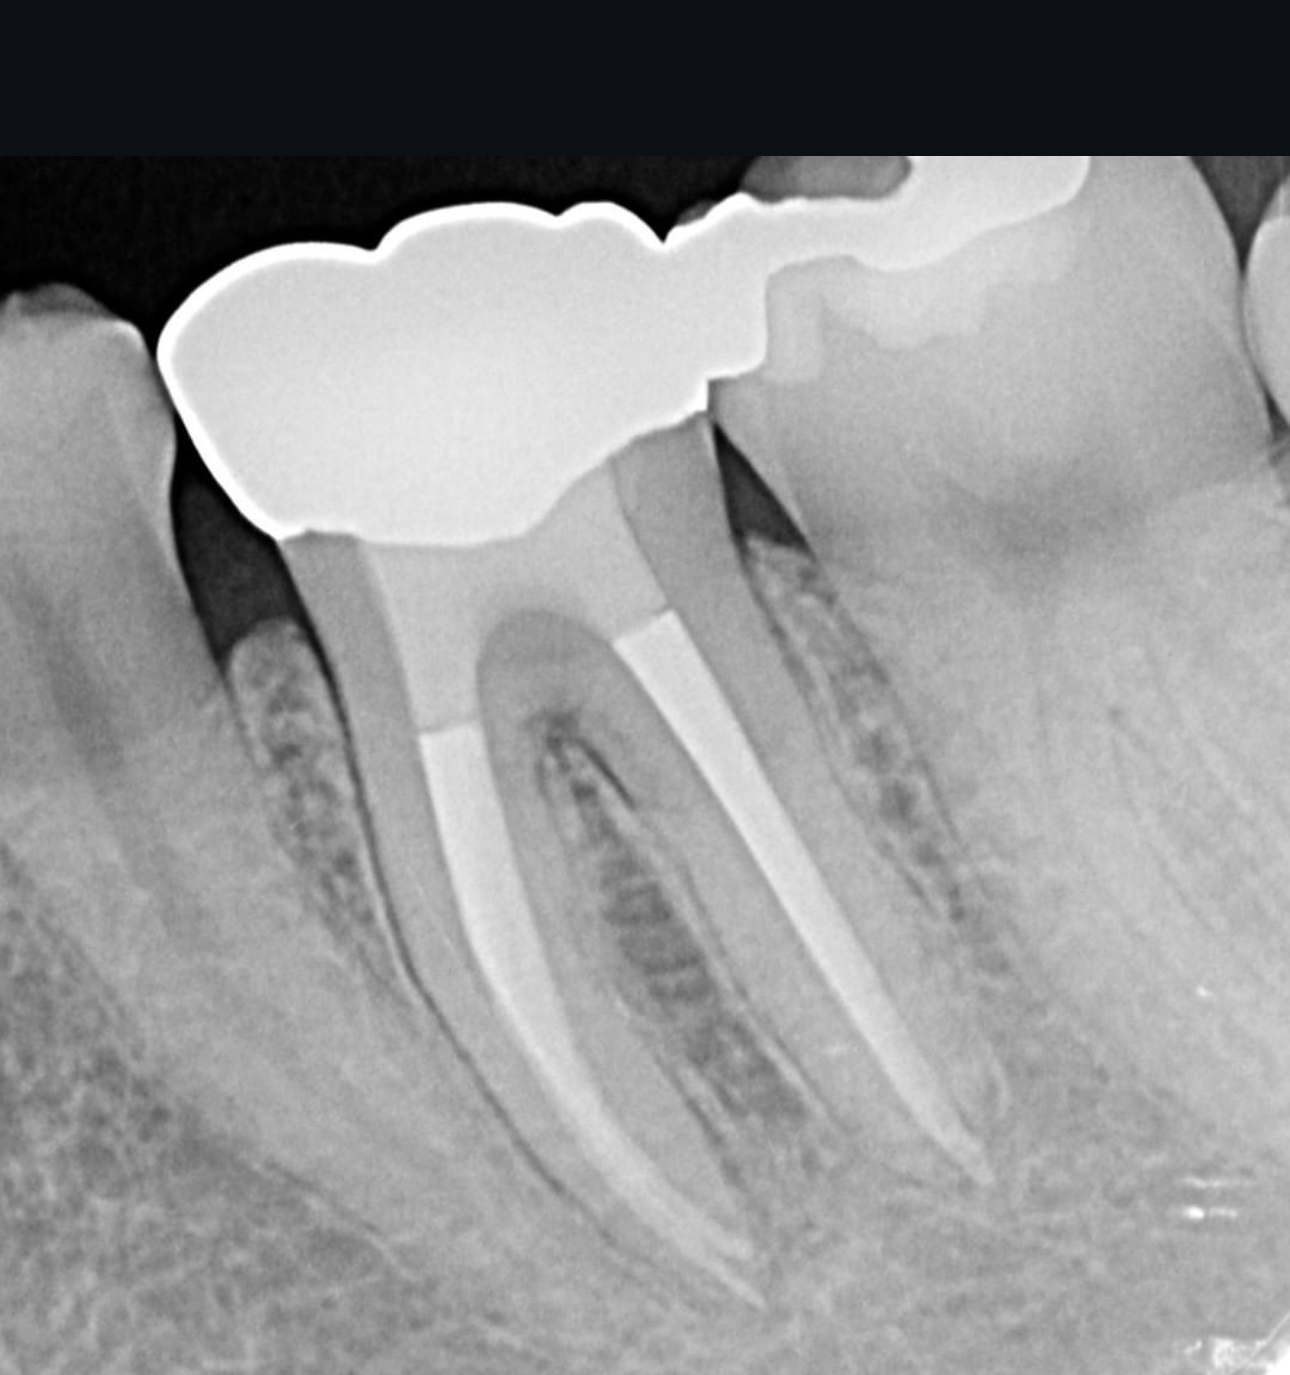

40代 男性

術前ですが左下6に大きな病変を認め膿がたまり抜歯が必要であるといわれ当院にお見えになりました。

根管治療術後2年です。膿の袋は綺麗に消失し被せ物が入り特に問題のない状態です。

費用 | 100000円 |

治療期間 | 6か月 |